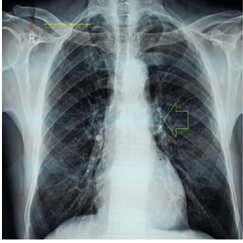

Figure 2a CXR film-PA.

A. CXR film-PA view was done on the day of the ICU admission showing small left hailer ground-glass opacity (lime arrow).

A 72-year-old married male farmer Egyptian patient was admitted to the intensive care unit (ICU) with angina, dizziness, and headaches, generalized skin rash within one hour after ingestion of a single sildenafil tablet (25mg). Circumoral numbness and extremities paresthesia were associated symptoms. He gave a recent history of mild fever, generalized myalgia, dry cough, and loss of smell within one week ago and after previous contact with a patient with COVID-19 pneumonia. He gave an old history of chronic obstructive pulmonary disease (COPD). Upon general physical examination; generally, the patient appeared thin, and long, had generalized body hives, look sweaty with an irregular pulse rate (VR of 72), blood pressure (BP) of 90/70 mmHg, respiratory rate of 18 bpm, a temperature of 37°C, and pulse oximeter of oxygen (O2) saturation of 95%. There is a barrel chest on chest inspection and generalized sibilant Ronchi were noted on the chest auscultation. Tests for provocative latent tetany were positive. No more relevant clinical data were noted during the clinical examination. The patient was admitted to the ICU with oral sildenafil-inducing angina. The patient urgently was treated in the ICU with high-flow O2 inhalation via O2 inhalation central system (100%, by simple mask, 10L/min), IM adrenaline 0.5 mg of 1:1000 (single dose), IV hydrocortisone vial (200 mg, then 100mg BID), IV chlorpheniramine maleate ampoule (20 mg, then 10mg BID), IV famotidine ampoule (40 mg, then 40mg BID), and IV Ringer solution (500ml, then 500ml BID). Aspirin; 4 oral tablets (75 mg, then OD), clopidogrel; 4 oral tablets (75 mg, then OD), enoxaparin SC (60 mg, BID), and atorvastatin (20 mg, OD) were added. The patient was hourly monitored for vital signs and O2 saturation. The initial ECG was done on the initial ECG on presentation in the ICU showing sinus arrhythmia (of VR: 70) with ST-segment depression in inferior leads, ST-segment elevation in anterioseptal leads, and evidence of physiological left axis deviation (LAD) (Figure 1A). The second ECG tracing was taken within 20 minutes of the above ECG tracing and after ICU admission showing normal sinus rhythm (NSR) with inferiolateral ST-segment depression, anterioseptal ST-segment elevation, and Wavy triple ECG sign (Yasser’s sign) (Figure 1B). The third ECG tracing was taken within a few seconds of the above ECG tracing and after ICU admission showing NSR (of VR 73) with ST-segment depression in aVF, and V4-6 leads and Wavy triple ECG sign (Yasser’s sign) (Figure 1C). The fourth ECG tracing taken within 2.5 hours after the ICU treatment showed sinus arrhythmia (of VR 64) and Wavy double ECG sign (Yasser’s sign; aVF and V5-6) with normalization of the above ST-segment deviations (Figure 1D). The initial complete blood count (CBC); Hb (15.3g/dl), RBCs (6.39*103/mm3), Hematocrit (44.3%), WBCs (9.6*103/mm3); (Neutrophils; 63.9 %, Lymphocytes: 29.0%, Monocytes; 4.3%, Eosinophils; 2.8% and Basophils 0%), Platelets; 159*103/mm3. SGPT was (39 U/L). Serum creatinine was (1.1mg/dl). RBS was (98 mg/dl). CRP was (9.6mg/dl). Ionized calcium was (3.83mg/d). The troponin test was negative. Chest x-ray was done on the day of the ICU admission showing small left hailer ground-glass opacity (Figure 2A). Later echocardiography showed a good LV systolic function of an EF of 61% and grade I diastolic dysfunction (Figure 2B). Sildenafil-inducing Kounis syndrome in the elderly with intertwining sinus arrhythmia, Wavy triple sign, Wavy double sign (Yasser’s signs), and mild COVID infection was the most probable diagnosis. Nearly complete recovery was achieved within 2.5 hours. The patient was discharged within 3 days of the above management after happening of dramatic improvement in both clinical and electrocardiographic ST-segment depressions and elevations. IV Hydrocortisone (100 mg BID), oral chlorpheniramine maleate (8 mg BID) for 3 days, aspirin tablets (75 mg, OD), oral calcium, and vitamin-D preparations (BID) for 30 days were prescribed on discharge with the recommendation for future cardiac and immunological follow-up.